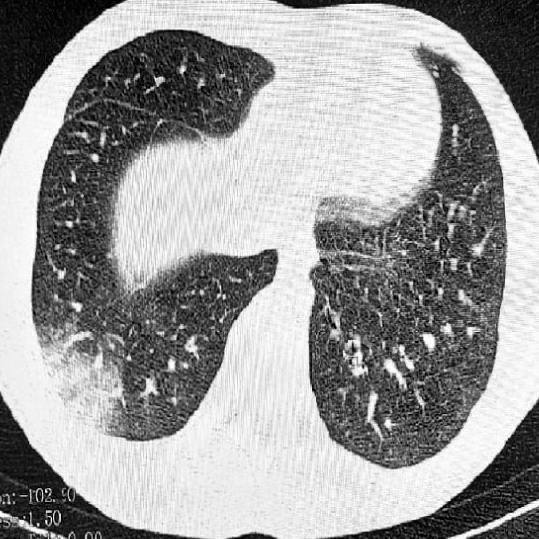

Впервые в стране выявлены случаи заболевания, связанного с вейпингом. Пострадали двое подростков из Томска: у одного диагностировали EVALI, а у второго — токсическое поражение нервной системы.